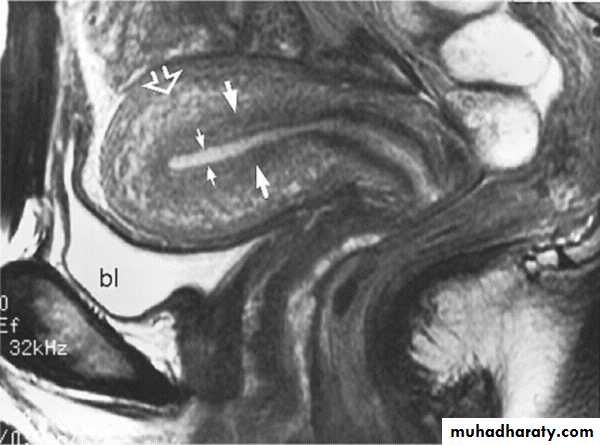

CONTRAST AGENT FOR MRIContrast agent providing useful diagnostic information with MRI .

The most widly used agents are gadolinium compounds which only cross the B.B.B. when it is damaged by disease and which concentrate in tissue and diseases processes with high blood supply .

Tissue which concentrate the agent show very high intensity ( they appear white ) on T1 –images .Tissue specific media ,such as iron oxide agents for reticuloendothelial cells imaging .